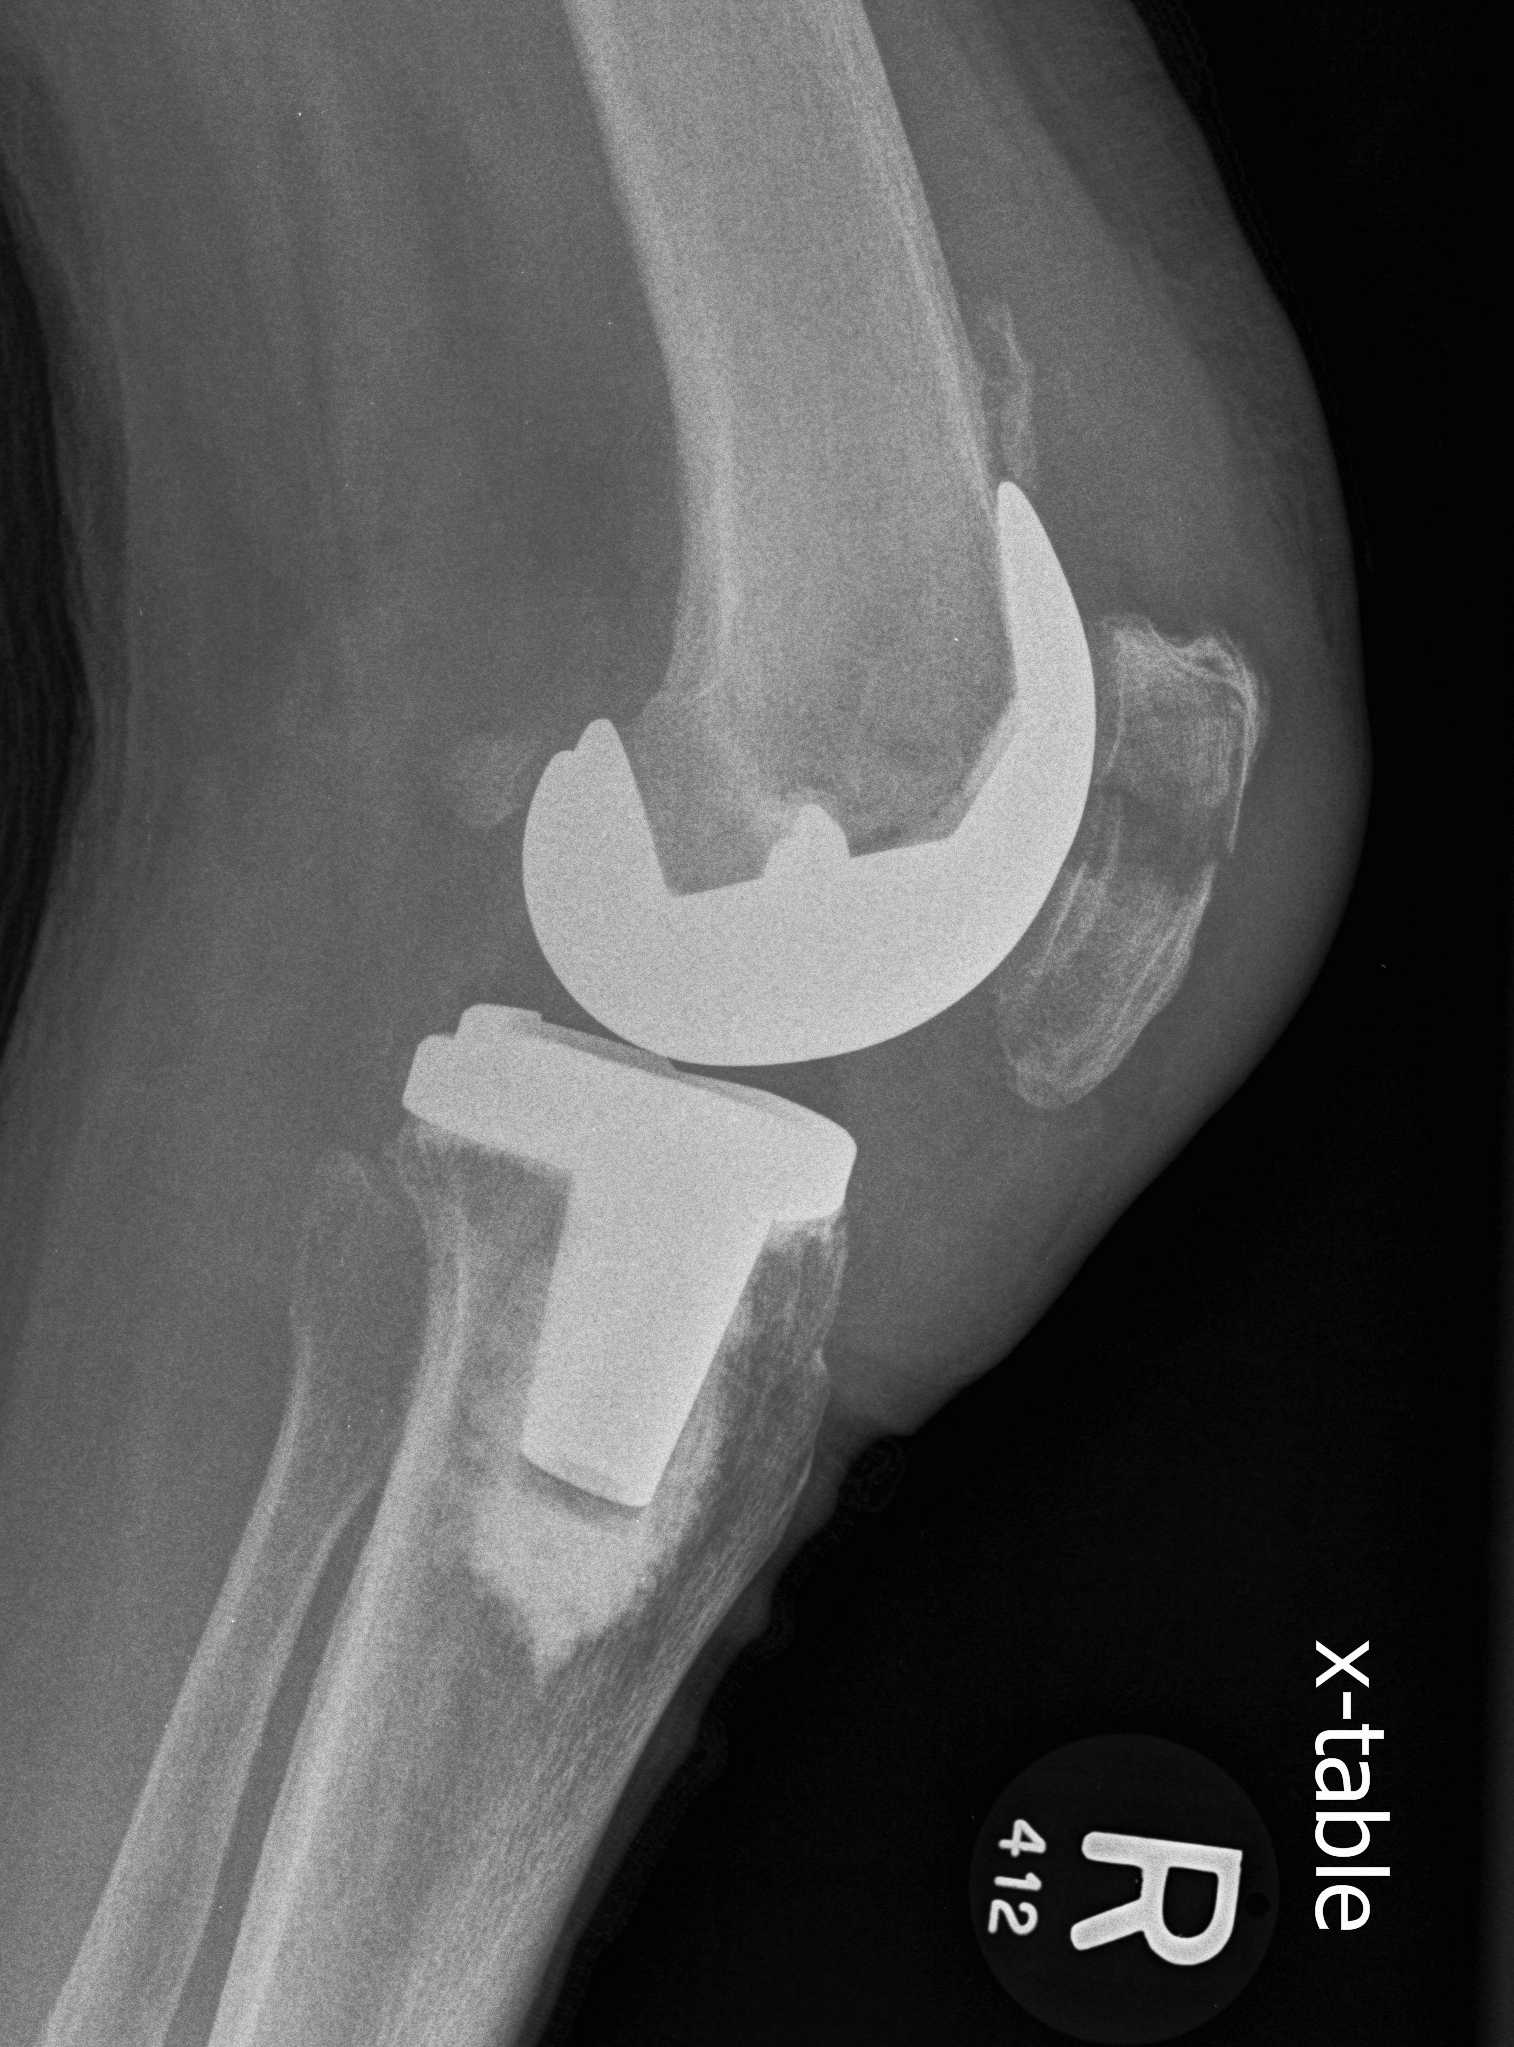

Surgical options

1. Lateral release + Patella resurfacing

2. Tibial tuberosity transfer +/- MPFL reconstruction

3. Revision

Options

- medialise patella component

- revise malrotated components